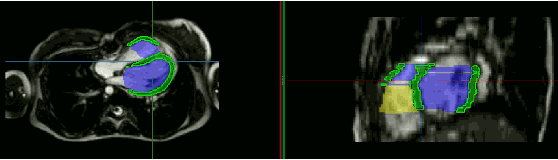

Abstract:Anisotropic multi-slice Cardiac Magnetic Resonance (CMR) Images are conventionally acquired in patient-specific short-axis (SAX) orientation. In specific cardiovascular diseases that affect right ventricular (RV) morphology, acquisitions in standard axial (AX) orientation are preferred by some investigators, due to potential superiority in RV volume measurement for treatment planning. Unfortunately, due to the rare occurrence of these diseases, data in this domain is scarce. Recent research in deep learning-based methods mainly focused on SAX CMR images and they had proven to be very successful. In this work, we show that there is a considerable domain shift between AX and SAX images, and therefore, direct application of existing models yield sub-optimal results on AX samples. We propose a novel unsupervised domain adaptation approach, which uses task-related probabilities in an attention mechanism. Beyond that, cycle consistency is imposed on the learned patient-individual 3D rigid transformation to improve stability when automatically re-sampling the AX images to SAX orientations. The network was trained on 122 registered 3D AX-SAX CMR volume pairs from a multi-centric patient cohort. A mean 3D Dice of $0.86\pm{0.06}$ for the left ventricle, $0.65\pm{0.08}$ for the myocardium, and $0.77\pm{0.10}$ for the right ventricle could be achieved. This is an improvement of $25\%$ in Dice for RV in comparison to direct application on axial slices. To conclude, our pre-trained task module has neither seen CMR images nor labels from the target domain, but is able to segment them after the domain gap is reduced. Code: https://github.com/Cardio-AI/3d-mri-domain-adaptation